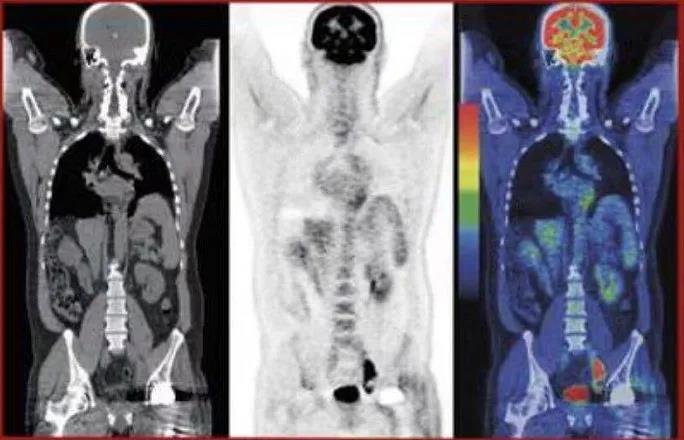

为什么做了PET/CT还需要做增强CT?

“为什么我做了最贵的PET/CT检查了还需要做增强CT呢?这是大部分患者在活检预约前提出的疑问,我们需要首先了解一下PET/CT和增强CT在疾病诊治过程中的作用及区别。PET/CT除了可以帮我们了解疾病原发灶之外,还可以评估是否已经向全身的淋巴结或其他器官发生了转移。因次,PET/CT它仅仅提示肿瘤发展的程度,有助于肿瘤的分期的判定。而对于肿瘤局部病灶的大小、性质、周围情况,增强CT能够清晰显示肿瘤周缘的血管、气管以及骨性组织等详细情况,有助于评价穿刺过程中避免大出血等严重穿刺并发症的发生风险。因而两者并不冲突,做了PET/CT后,仍然需要患者再做增强CT。

那么,对于刚做过PET/CT检查的患者马上可以做穿刺活检术么?从防护角度而言,患者当天进行了PET/CT或骨扫描检查后,体内存有带放射性的药物示踪剂,对周围人员有一定的辐射性,因而需要等待适当的时间(PET/CT后24小时、骨扫描后48小时)来完成穿刺活检诊疗。